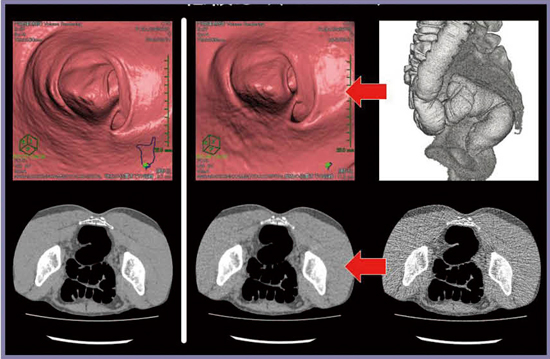

■症例4:56歳,男性

便潜血検査陽性で,大腸CTを施行した(図4a)。前処置,拡張も良好で,正常と判断されたが,同日に行われた内視鏡検査において,下行結腸に表面型病変が指摘された(図4b)。

図4 症例4

a:大腸CT b:内視鏡像